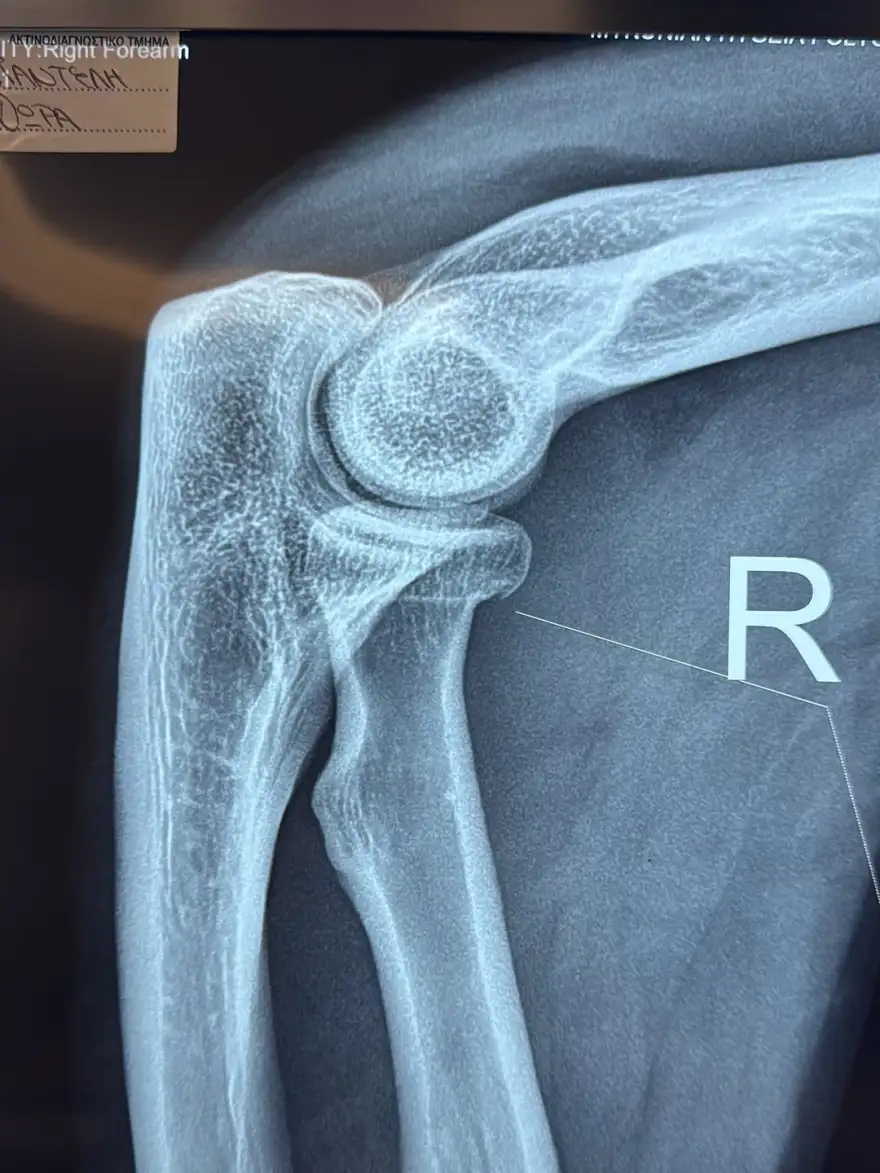

Ακολούθως, καθησύχασε τους διαδικτυακούς της φίλους, εξηγώντας πως παρότι υπέστη κάποιους τραυματισμούς, τόσο η ίδια όσο και το μωρό της είναι καλά στην υγεία τους. «Το μωράκι μου και εγώ είμαστε καλά και το μόνο που μου έμεινε από όλο αυτό είναι ένα ρωγμώδες κάταγμα στο χέρι, ένα αιμάτωμα στον αγκώνα και ένα στον ώμο και μερικές μελανιές στο γόνατο», αποκάλυψε με ειλικρίνεια.